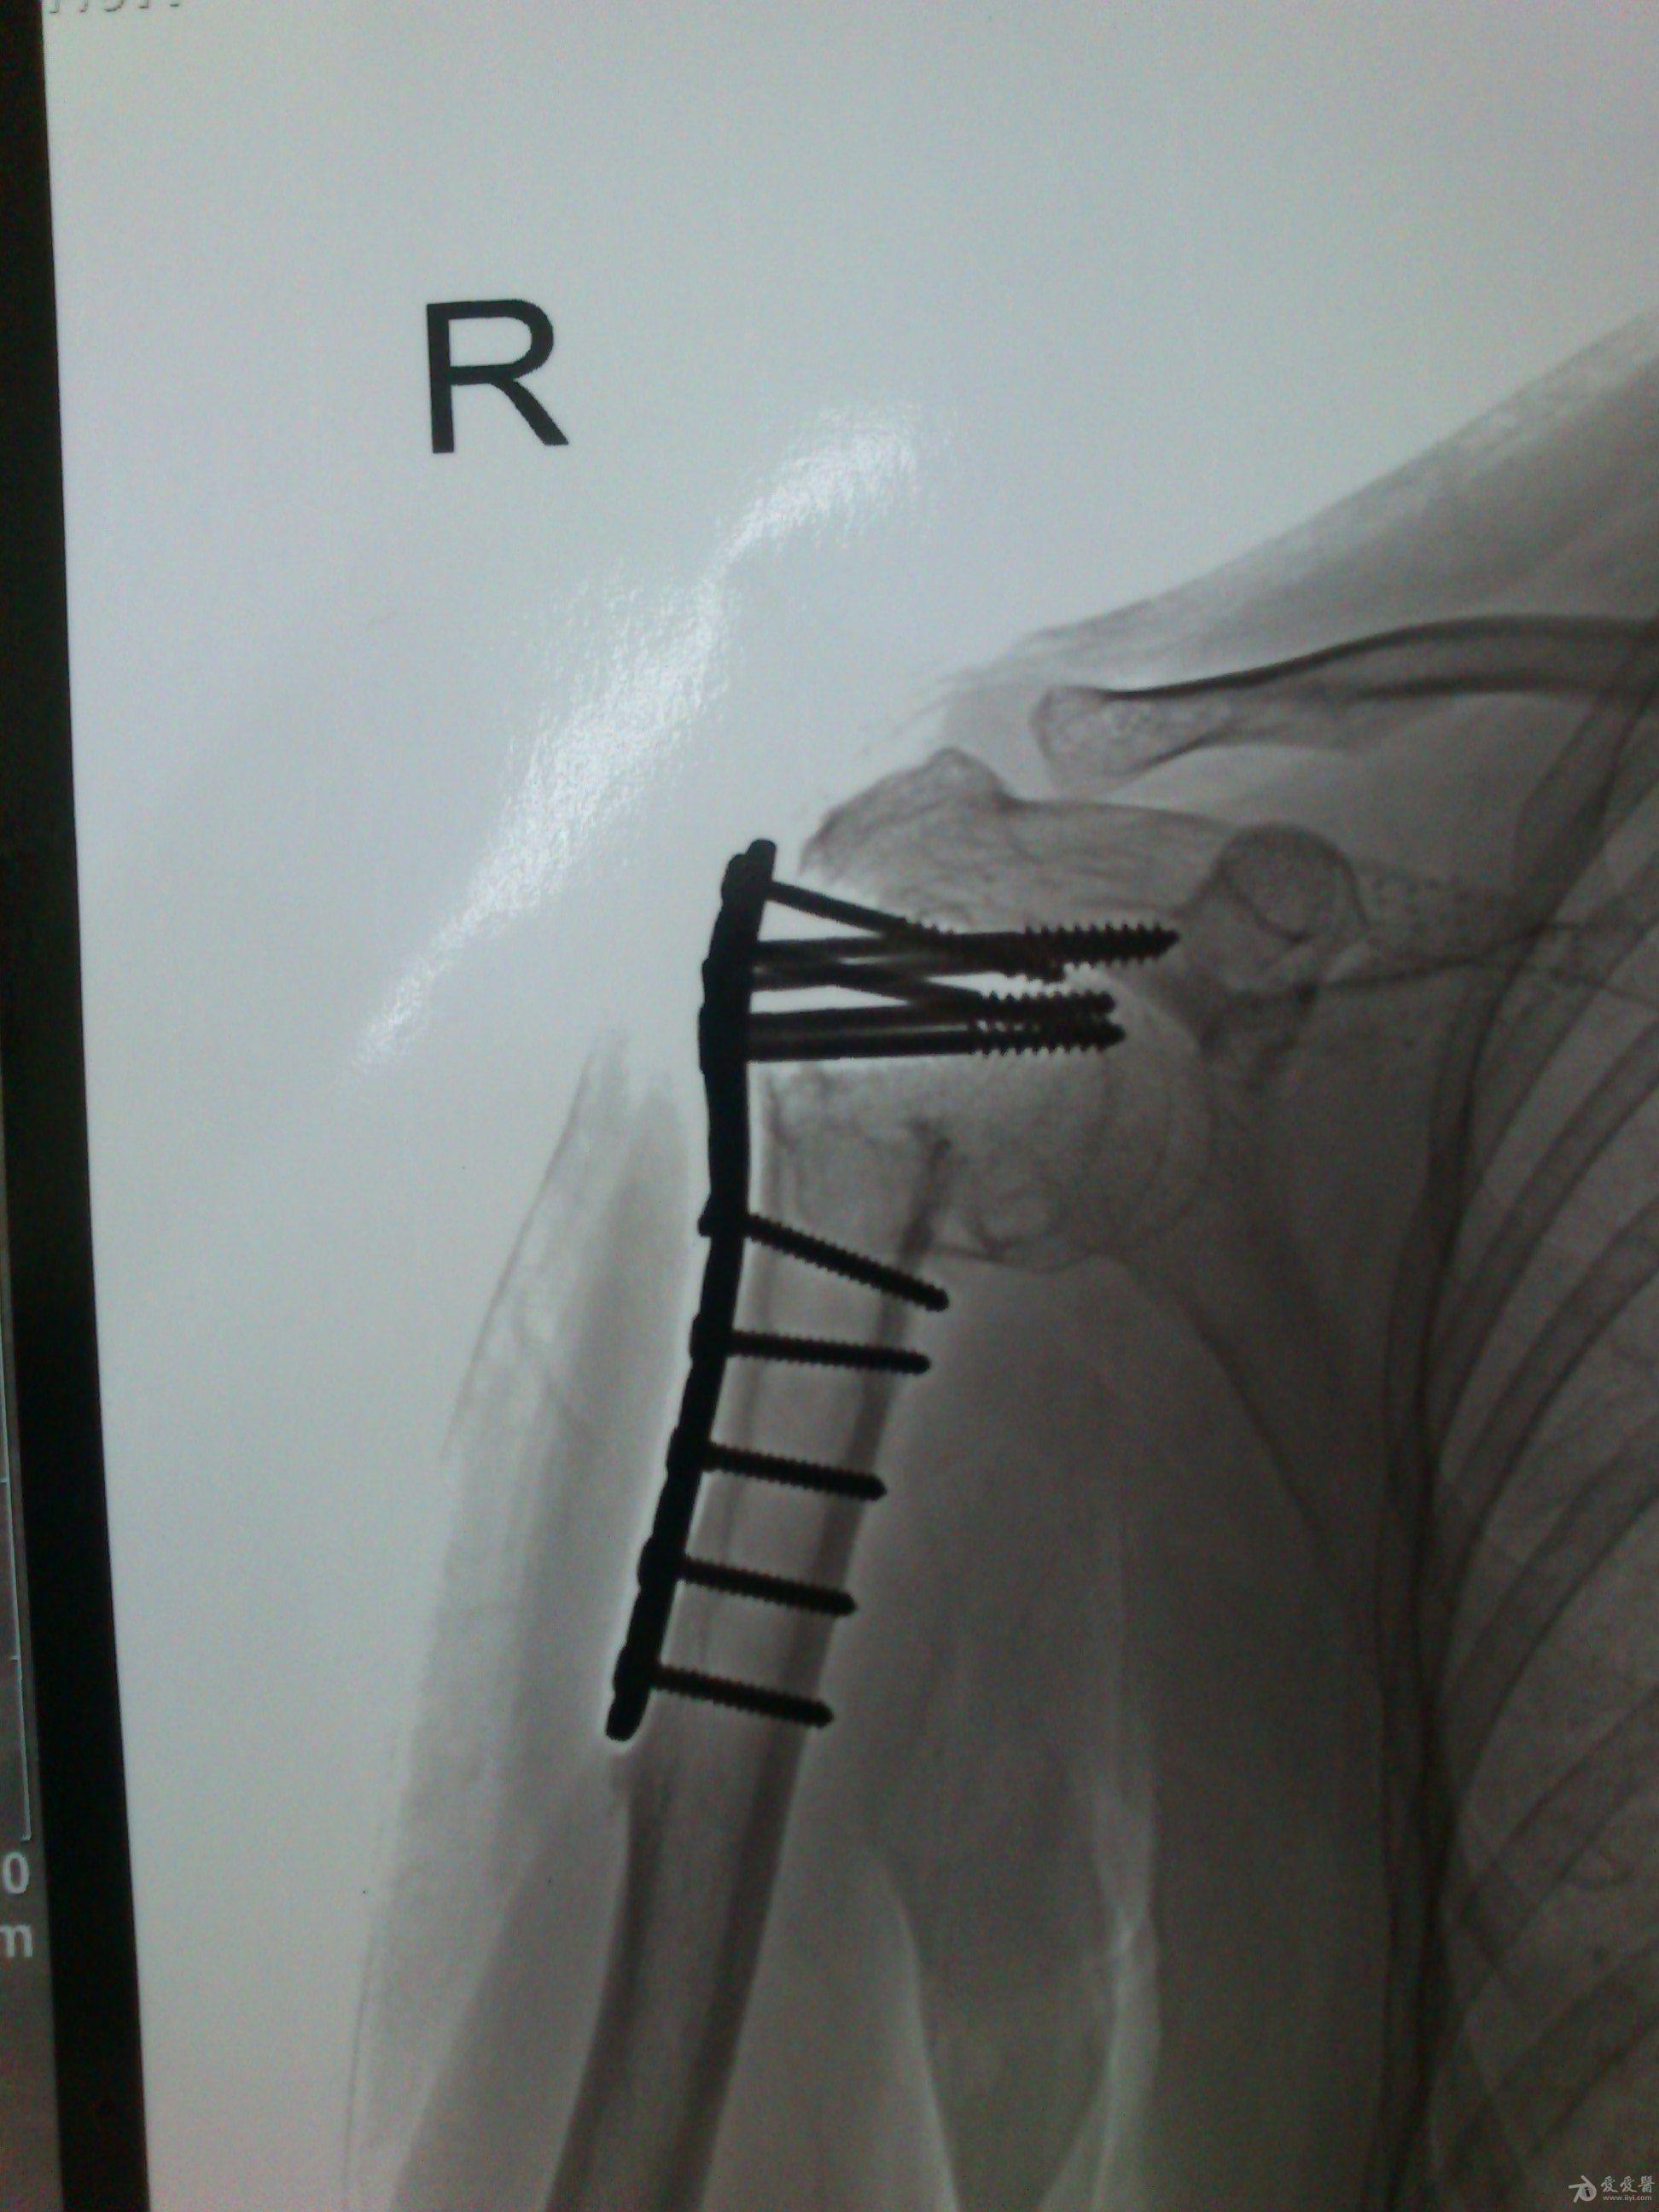

病史特点及病情摘要:1、患者女性,51岁。2、患者自诉入院前1年余因右肱骨外科颈骨折在外院行切开复位内固定术,术后右肩关节疼痛、活动受限,一直未予处理,今为明确诊治入院。患者精神、食欲、睡眠尚可。3、既往史、个人史、家族史无特殊。4、入院查体:生命征平稳,心肺腹检查未见异常,NS(-)。专科情况:右上臂近端内侧见一约15cm手术切口疤痕,愈合佳,右肩关节能外展20度,前屈、后伸及旋前、旋后功能障碍,余关节活动好。舌质红,苔薄白,脉实。5、辅助检查:右肩关节正侧位片:右肱骨外科颈骨折内固定术后再骨折伴右肩关节脱位。

诊断:右肱骨外科颈骨折内固定术后再骨折伴右肩关节脱位

诊疗计划:????前两张片是院外术前,中间两张是院外术后,后两张是在我院照。 术前

院外术后